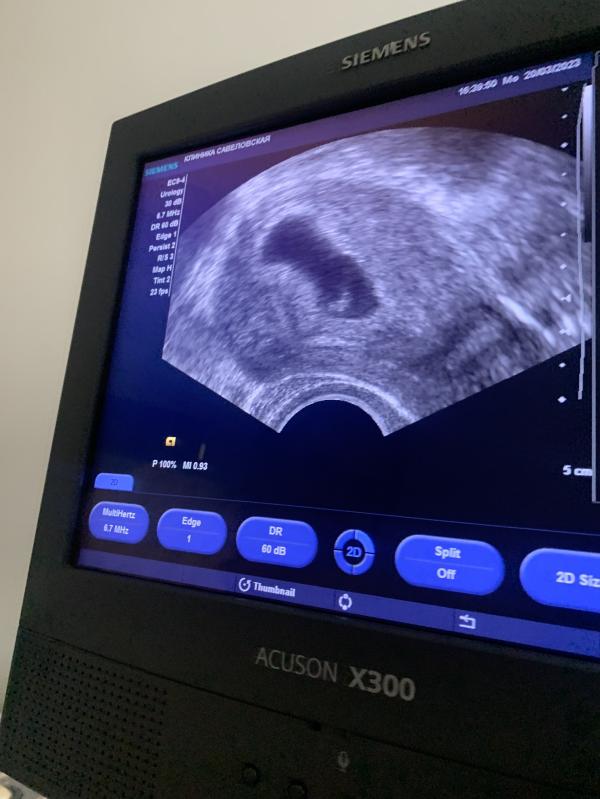

УЗИ на 26 ДПП: КТР 3.9 мм, СБ+, ЖМ 4.1 мм - как дела у моей крохи? Делимся опытом!

КРТ 3.9мм

СБ+

ЖМ 4.1 мм

26 ДПП